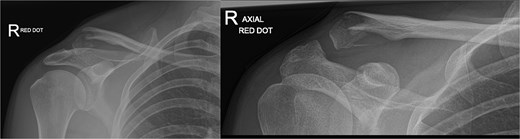

A 15-year-old male sustained a displaced Neer type IV lateral clavicle fracture during a rugby match, presenting with acute pain, deformity, and dorsal displacement without neurovascular compromise (Fig. 1). Imaging confirmed the diagnosis, and open reduction with TightRope and Fiber-wire reinforcement was performed. Early rehabilitation was initiated following short-term immobilization. At 6 weeks, the patient achieved pain-free shoulder function and radiographic stability. By four months, he regained full range of motion and returned to non-contact sports. Minor peri-scar numbness persisted, but imaging confirmed fracture union, and he was cleared for contact activities (Fig. 2A–B).

Radiographs of first case showing a displaced Neer type IV lateral clavicle fracture with deformity and displacement.